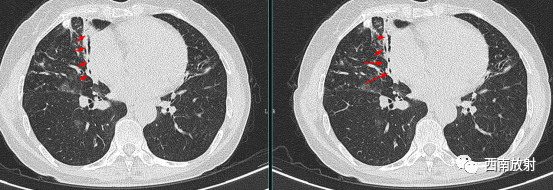

当扩大的支气管走行与扫描图像层面平行时,表现为轨道征。扫描层面有时与支气管不垂直或平行时,可以通过图像重建弥补。

▲图:右肺中叶炎症导致静脉曲张样支气管扩张,双轨征;